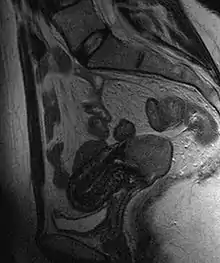

Cervical cancer seen on a T2-weighted sagittal MR image of the pelvis

Often before the biopsy, the doctor asks for medical imaging to rule out other causes of woman's symptoms. Imaging modalities such as ultrasound, CT scan, and MRI have been used to look for alternating disease, spread of the tumor, and effect on adjacent structures. Typically, they appear as heterogeneous mass on the cervix.[47]